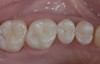

Strong and durable adhesion to tooth substrate is critical for clinical long-term success of resin-bonded direct and indirect restorations. Resin-composite restorative materials are applied directly in the oral cavity (Figure 1 and Figure 2) but undergo a certain degree of shrinkage on polymerization, resulting in the possible formation of a gap at the resin/tooth interface. Bonding agents, paired with the application of resin composites, attempt to seal the interface between the cavity and the restorative material, thus reducing the risk of interfacial gap formation, marginal leakage, postoperative sensitivity, and recurrent caries.